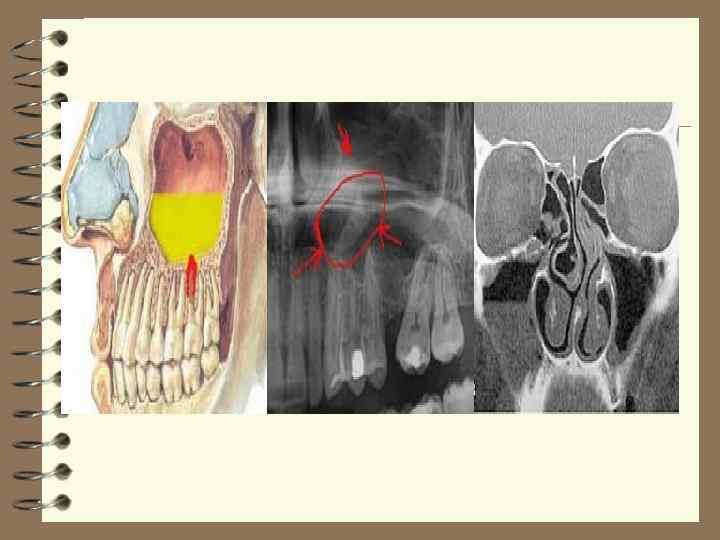

Риноскопияға қосымша әдістердің бірі В. И. Воячек ұсынған диафоноскопия болып есептеледі. Қараңғыланған бөлмеге науқасты отырғызып, ауыз қуысына кішкене электр шамын немесе диафоноскопты енгізіп еріндердің толық жабуын өтінеді. Осыдан кейін шамды жаққанда сау жағындағы тіндер және көз жанары қызарады, ауырған жағы қараңғы болып қалады. Ал, науқас сәулені тек сау жағымен сезінеді. Жоғарғы жақ сүйегі қуысының ауруларын тексергенде рентгенография әдісі өте бағалы мағлұматтар береді. Әдетте қуыс іші толған, сондықтан рентген сәулесін кедергісіз өткізеді де рентгенограммада ашық болып көрінеді. Егер Гаймор қуысында сулы-ірің немесе басқа заттар болса рентген сәулесі тосқауылға тоқтап рентгенограммада бұлдыр немесе қараңғы болып көрінеді. Егер, жоғарғы жақ қуысында сұйық ірің жиналса рентгенографияны науқасты тұрғызып жасағанда оның деңгейін байқауға болады. Қуыстың кілегей қабығы домбықса қабырға көлеңкесі тәріздес көрінеді. Одонтогенді гайморитте бұл айтылған көріністер тек бір жағында орналасып, басқа қосалқы мұрын қуыстары таза болады. Рентгенографияны сәуле тоқтататын (контрасты) сұйық заттармен жасағанда аурудың көлемін және сипатын көрумен қатар, дұрыс ем қолданылуын қамтамасыз етеді. Томография әдісі аурудың қай қабатта жатқанын, оның орналасуынтопографиясын анықтайды. Қазіргі кезде компьютерлік томография әдісі Гаймор қуысында кездесетін ауруларды анықтауға үлкен көмегін тигізеді.

Клиникалық көрінісін рентгенографиялық зерттеу дәлелдейді. Рентген суретте Гаймор қуысының күңгірттенгені анықталады. Іріңді түрі куңгірттенуінің біріңғай күшейе түсуімен сипатталады, ал полипозды түрінде Гаймор қуысында перде тәрізді және көлемі әр түрлі көлеңке көрінеді. Ауыз қуысының рентген суретінде тіс түбірлерінің қуысқа қатынасы олардың айналасындағы тіндердегі өзгерістер гранулема (киста) сарысулы ісік анық көрінеді. Созылмалы гаймориттерде өзгеріске ұшыраған қуыстағы шырышты қабаттың орналасқан жерін, оның көлемін және сын-сипатын анықтау үшін контрасты рентгеноскопия әдісі өте тиімді. Контрасты зат ретінде 3 -7 мл йодлипол қолданылады. Созылмалы одонтогенді гайморитті Гаймор қуысының шырышты қабатының қатерлі ісігінен ажырата білген жөн. Тұрақсыз белгілерден басқа қатерлі ісік болған жағдайда рентген суретінде Гаймор қуысы қабырғаларының бүлінуі-деструкциясы көрінеді. Толық дұрыс нақтама қою үшін эндоназалды биопсия немесе гайморотомия отасында алынған тінді гистологиялық зерттеу жүргізу керек. Гаймор қуысындағы одонтогенді қабыну кезеңін басқа да ісіктерден (саркома, остеома, амелобластома, сарысулы ісік) айыра білу керек. Созылмалы одонтогенді гайморитті парадентарлы Гаймор қуысы қабырғасын жоғары және артқа ығыстырып өсетін сары-сулы ісіктен ажырату керек. Бұл жағдайда мұрыннан су ақпайды. Рентгенограммада ісік анық шектелген, ал пункция жасаса жылтырақ ірің алуға болады. Осымен қатар одонтогенді гайморит Гаймор қуысының шырышты қабатының созылмалы аллергиялық қабынуына ұқсайтынын есте сақтау керек. Аллергиялық гайморитпен ауырған науқастардың талдауында, аллергиялық экзема, ңейродермит, коньюнктивит, Квинке ісінуі, эксудативті диатез (тамаққа немесе дәрі-дәрмектерге) бар екені анықталады. Аллергиялық гаймориттерде одонтогенді ошаққа байланысты ауыру сезімі болмайды, ауру өте ұзаққа созылу мерзімі тән болып, өте көп мөлшерде мұрыннан мөлдір қою су бөлінеді. Мұрынның шырышты қабаты күрт ісініп көгереді.